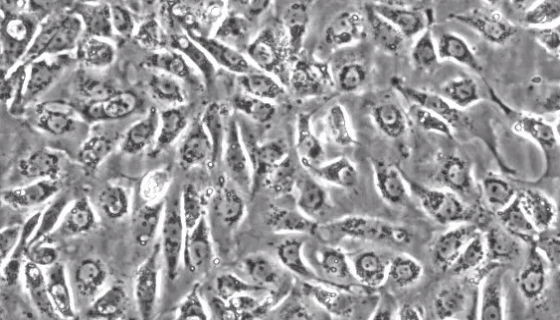

人肺泡上皮细胞的背景与概述及相关研究!

人肺泡上皮细胞由肺泡I型和Ⅱ型上皮细胞组成,线性分布于肺内9...